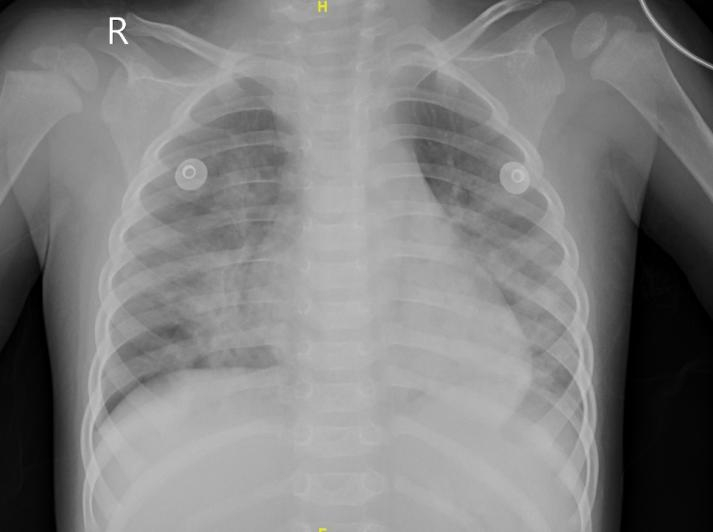

患者入院后给予洗胃,洗出少量暗红色液体,伴间断恶心,禁食留置胃管。伴间断发热,最高39 ℃,呼吸急促,阵发性咳嗽,肺部闻及粗湿啰音,血气分析提示低氧血症,面罩吸氧(5 L/min)状态下血氧饱和度维持不佳,改为持续气道正压通气(continuous positive airway pressure, CPAP)无创呼吸机辅助通气,结合相关辅助检查,考虑肺部感染,给予哌拉西林他唑巴坦1.125 g静滴每8 h一次(Q8H),14 d后停用;氨溴索注射液7.5 mg静滴Q12H,14 d后停用;布地奈德混悬液1 mg联合硫酸特布他林2.5 mg雾化吸入Q6H治疗,12 d后减量为Q12H,14 d后停用;应用20%甘露醇注射液40 mL静滴Q8H,3 d后减量为Q12H,4 d后减量为QD,6 d后停用;甲泼尼龙26 mg静滴QD,5 d后停用;奥美拉唑10 mg静滴QD,3 d后停用,磷酸肌酸钠0.5 g静滴QD,12 d后停用;余对症支持治疗。经治疗未再惊厥发作,住院第2天恶心好转,经口喂养可耐受,CPAP辅助呼吸4 d后停用,呼吸急促症状好转,自主呼吸状态下血氧饱和度监测正常;住院第8天复查视频脑电图未见异常;住院第10天体温正常,咳嗽好转,肺部CT提示双肺多发斑片状密度增高影,边缘模糊,段及段以上支气管通畅(图 2A)。住院15 d临床症状恢复出院。出院后2周复诊,患者已无临床症状,复查肺部CT提示双肺支气管血管束增粗伴透光度欠均,小斑片影及索条影较前好转(图 2B)。

| 注:A为患者病程第10天,B为患者病程第30天 图 2 患者胸部CT影像学变化 |